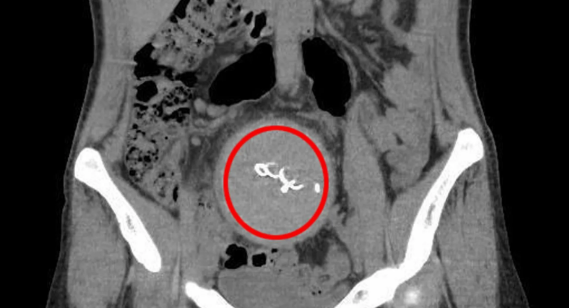

Belə ki, 2 ildir ağrılar və irin axıntısı davam edib. Bu müddət ərzində müraciət etdiyi xəstəxanalardan heç bir nəticə ala bilməyən gənc qadın 2 il ağrıdan sonra 2 ay əvvəl Antalya Təhsil və Araşdırma Xəstəxanasına müraciət edib. 2 il əvvəl uşaq dünyaya gətirən qadın davamlı ağrılar səbəbilə müraciət etdiyi xəstəxanada qarnında steril parça unudulduğunu öyrənib. Çəkdiyi ağrıdan uşağını belə yedirə bilmədiklərini bildirən qadın xəstəxananı və həkimi məhkəməyə verəcəyini bildirib./BiG.AZ